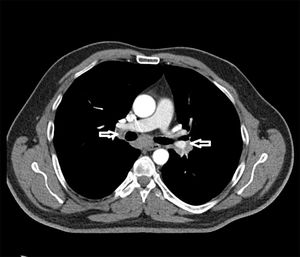

Case Report45 years old male patient diagnosed and follow-up with sarcoidosis applied to our clinic because of pain and swelling of the both ankle joints and swelling, redness and tenderness of the left first MTP joint. During examination, the patient described that previously had similar attacks in first MTP joints. Patient's physical examination showed; sensitivity of both ankle joints and swelling, redness and reduced range of motion of left first MTP joint. On laboratory tests; the acute phase reactants, serum uric acid and serum angiotensin converting enzyme (ACE) level were high (Table 1). On radiological examinations; there is no pathology on the radiograph of the ankle and toes except soft tissue swelling. Chest radiography showed enlargement in both hilar area (Fig. 1) while thorax CT showed bilateral hilar lymphadenopathy (Fig. 2). Abdominal ultrasound was normal. Serological tests was performed, negative results for rheumatoid factor (RF), antinuclear antibody (ANA), anti-cyclic citrullinated peptide antibody (anti-CCP Ab), anti-neutrophil cytoplasmic antibody (ANCA), anti-dsDNA were determined. Hepatitis markers (HBV, HCV, HIV) were normal. Monosodium urate (MSU) crystals were showed in the fluid analysis of the joint puncture. He has diagnosed with gouty arthritis and sarcoidosis according to clinical, laboratory and radiologic evaluations. Treatment with low-dose corticosteroids (prednisolone 4mg/day) and colchicine were initiated. One month later the patient complaints and laboratory findings were regressed. Six month later the radiological regression was observed on the control torax CT.